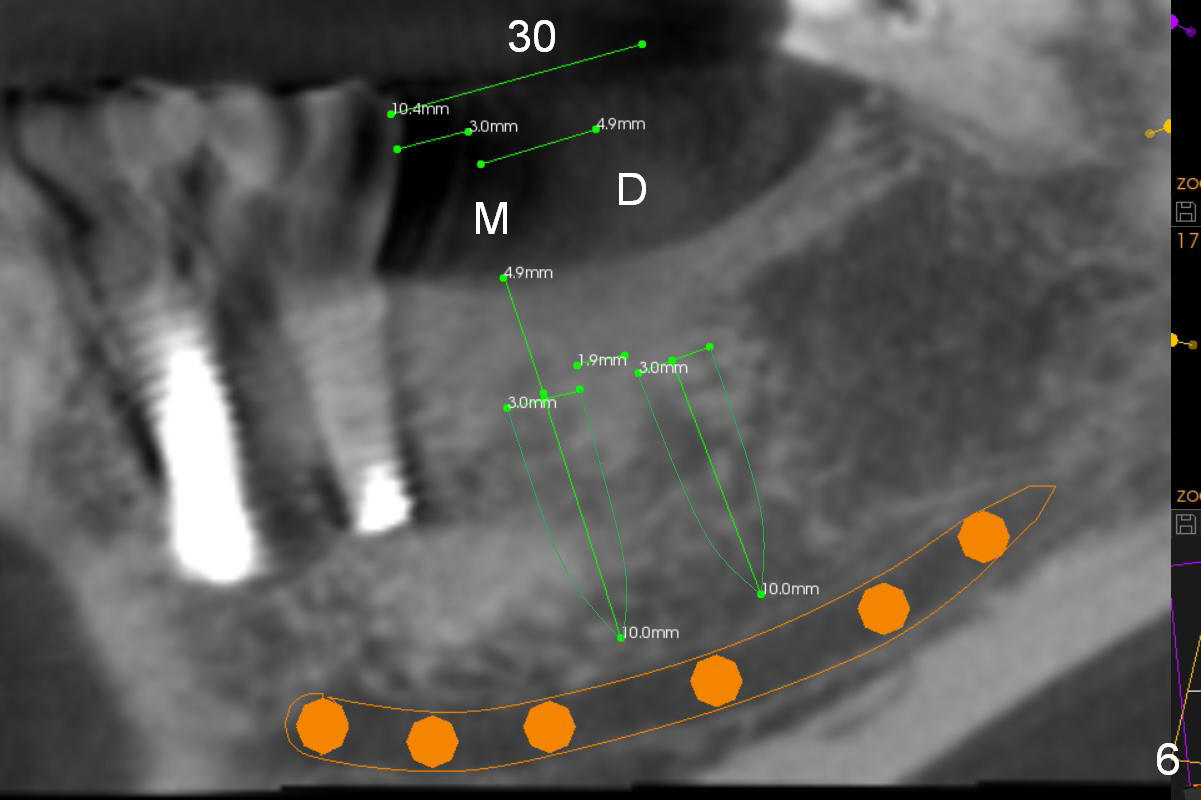

Narrow Ridge at Lower 1st Molar

A 56-year-old woman will return for #30 implant placement.  The ridge is narrow and pointed at the top.  If a 4 mm implant is placed, the ridge has to be reduced for 5.5 mm and the implant will be as short as 9 mm (Fig.1).  When 2 of 3 mm 1-piece implants are used, they can be placed higher (Fig.2,3,6).  It may be less likely to perforate the buccal plate if 2.5 mm 1-piece implants are placed (Fig.4,5,7).